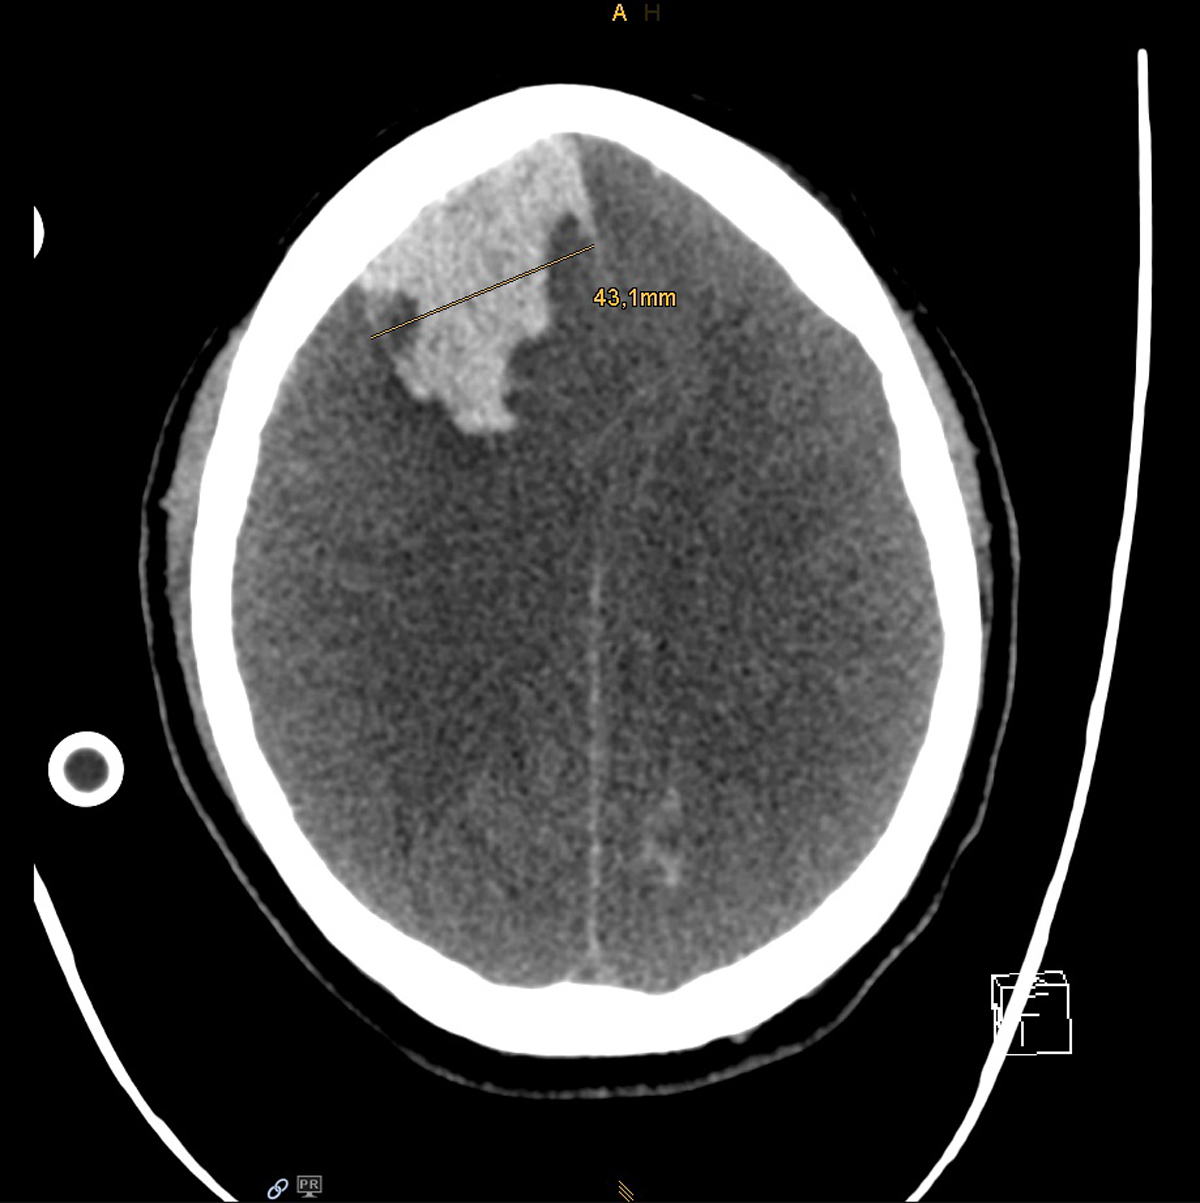

Eleven days after initial onset of symptoms, bilateral, widened pupils non-reactive to light were noted on routine physical examination. CT scan of the brain revealed a large intra-parenchymal haemorrhage located in the right frontal lobe with consequent compression of the ventricles, transtentorial and subfalcine herniation, and generalised cerebral oedema (supplementary fig. S2). Predisposing factors for such catastrophic bleeding were thrombocytopenia (Nadir 37 G/l), owed to extracorporeal therapies (vv-ECMO and CVVHD), necessary anticoagulation and sepsis. Notably, activated clotting time was in the recommended range of 150–180 sec. In consideration of septic multi-organ failure and a futile neurological prognosis, the treating clinicians together with the patient’s family decided to shift from medical to palliative care and the patient passed away after withdrawal of ECMO.

Figure S2 Patient 1: Computed tomography scan of the brain showing acute intraparenchymal bleeding in the right frontal lobe and generalised cerebral oedema.